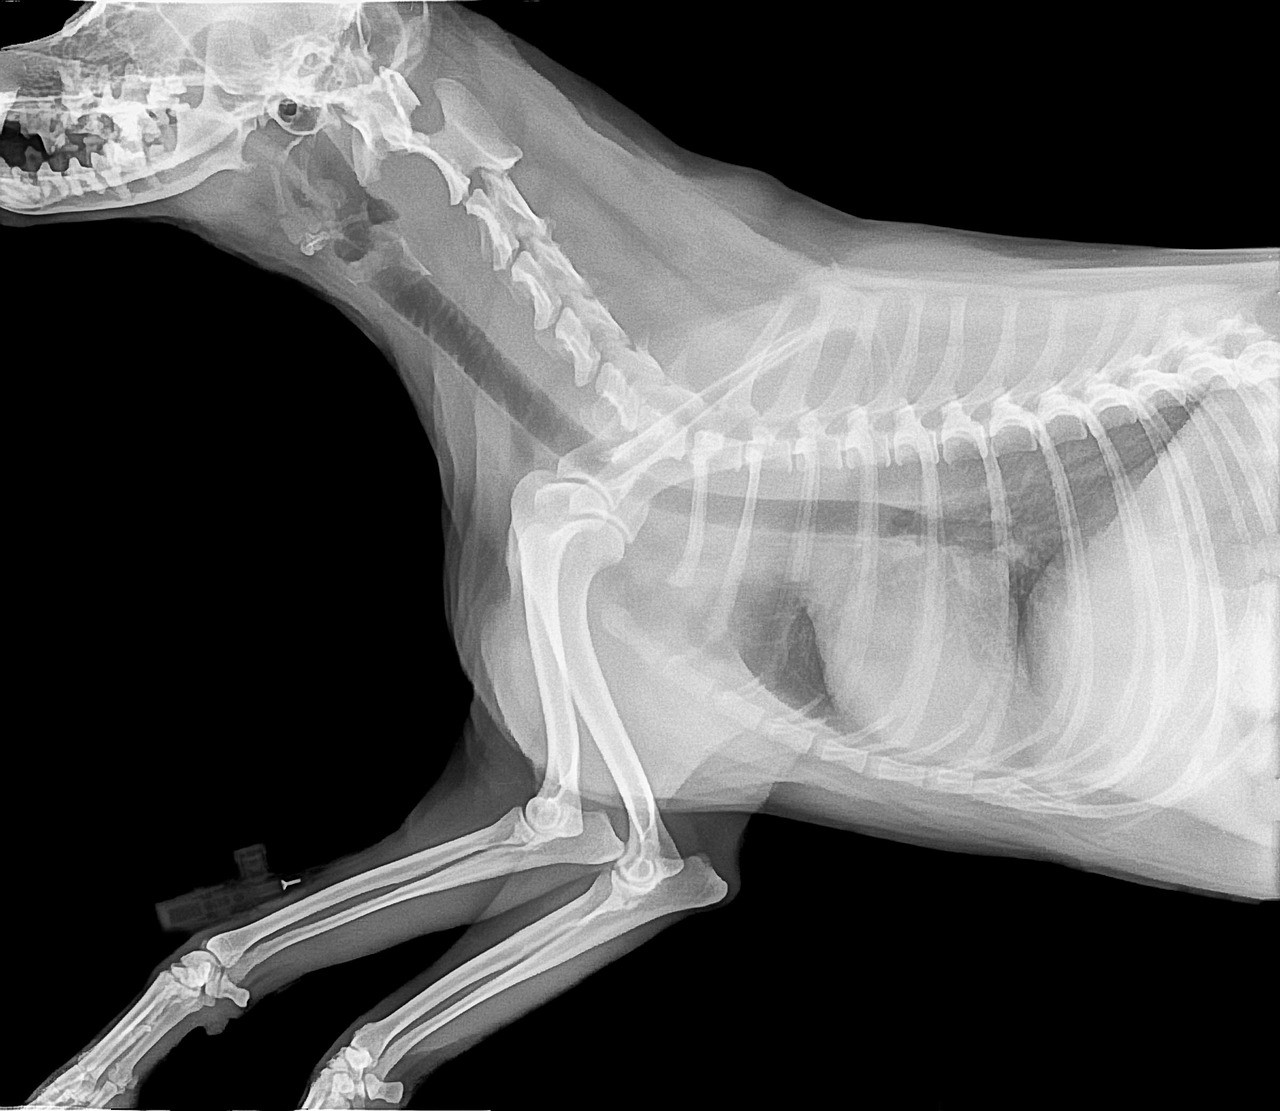

반려견이 걸릴 수 있는 질병은 다양합니다. 대표적으로는 심장사상충, 피부병, 귀염증, 위장관 질환 등이 있습니다. 특히, 심장사상충은 모기를 통해 전파되므로 여름철에 더욱 주의해야 합니다. 피부병은 습한 환경에서 쉽게 발생할 수 있으며, 귀염증은 귀 안쪽에 염증이 생기는 질병입니다. 이러한 질병들은 조기에 발견하고 치료하는 것이 중요합니다.

각 질병마다 나타나는 증상이 다릅니다. 예를 들어, 심장사상충에 감염된 반려견은 기침, 무기력, 체중 감소 등의 증상을 보일 수 있습니다. 피부병의 경우에는 가려움증, 발진, 탈모 등이 나타납니다. 귀염증은 귀를 자주 긁거나 흔드는 행동으로 나타나며, 심한 경우에는 귀에서 악취가 나기도 합니다. 이러한 증상을 발견하면 즉시 수의사와 상담하는 것이 좋습니다.

질병에 따라 치료 방법이 다릅니다. 피부병의 경우에는 항생제나 항진균제를 사용하여 치료할 수 있습니다. 귀염증은 귀 세척과 함께 항생제를 사용하여 치료합니다. 심장사상충은 예방이 가장 중요하지만, 감염된 경우에는 약물 치료가 필요합니다. 이러한 치료는 반드시 수의사의 지시에 따라 진행해야 합니다.